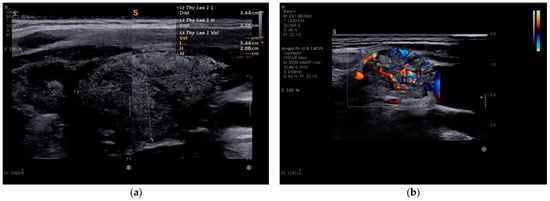

Multiparametric Ultrasound Features of the Diffuse Sclerosing Variant of Papillary Thyroid Carcinoma: A Single-Center Case Series

Background/Objectives: The diffuse sclerosing variant of papillary thyroid carcinoma (DSV-PTC) is a rare and aggressive subtype characterized by diffuse gland involvement and early cervical lymph node metastasis. Preoperative differentiation from classic papillary thyroid carcinoma and autoimmune thyroid disease remains challenging on B-mode ultrasound. This study aimed to describe the multiparametric ultrasound features of DSV-PTC in a single-center case series and highlight practical imaging insights. Methods: We retrospectively reviewed seven consecutive patients with histologically confirmed DSV-PTC evaluated at a single center between 2013 and 2025. All patients underwent standardized B-mode ultrasound, color Doppler, and two-dimensional shear-wave elastography prior to surgery. Clinical, autoimmune, cytological, surgical, pathological, and follow-up data were analyzed descriptively. Results: The cohort included five females and two males (mean age 28 years). Autoimmune thyroid disease was present in three patients. High-risk ultrasound features were identified in all cases, with microcalcifications in six patients and a diffuse “snowstorm” appearance in five. Elastography demonstrated increased stiffness in six out of seven lesions (Emean 28–173 kPa; Emax 31–300 kPa). Cervical lymph node metastases were confirmed in all patients. In two cases, elastography aided identification of focal malignant involvement within diffusely altered thyroid parenchyma. All patients underwent total thyroidectomy with central neck dissection; lateral neck dissection and radioiodine therapy were performed selectively. No distant metastases were detected. Conclusions: In this case series, DSV-PTC showed a characteristic multiparametric ultrasound pattern combining high-risk B-mode features with frequently increased tissue stiffness. Elastography provided complementary information, particularly in the presence of autoimmune thyroid disease, by helping localize focal malignant involvement within diffusely altered parenchyma. Full article

Show Figures

Figure 1